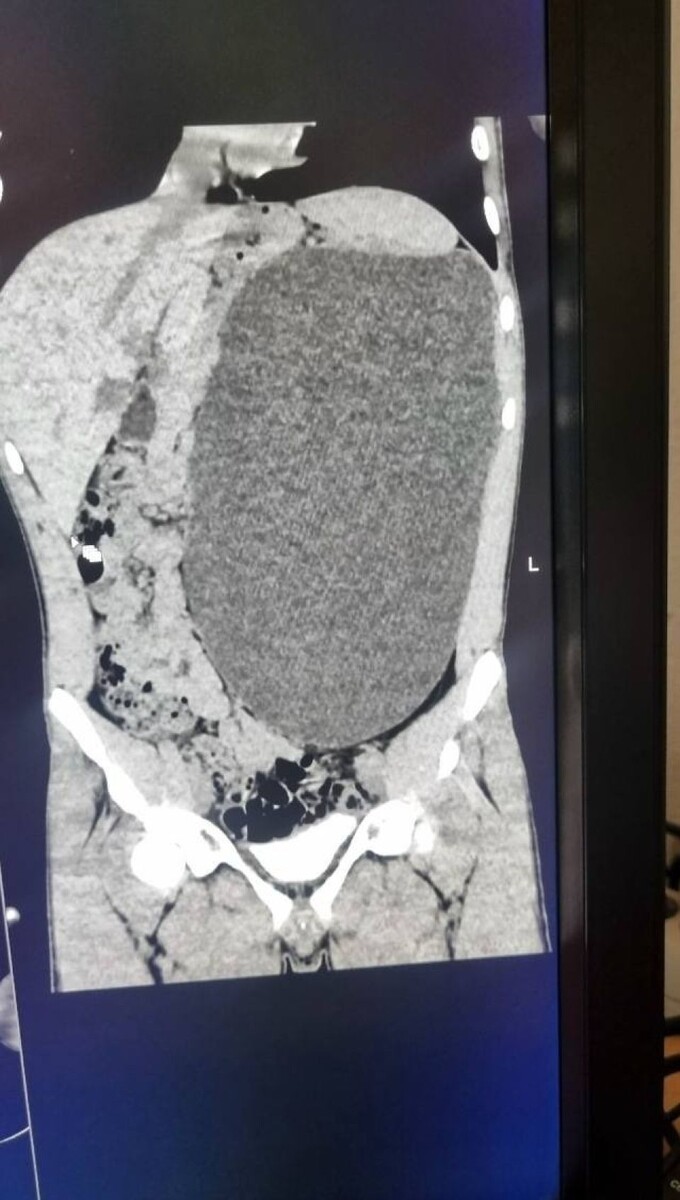

В Новосибирске плановое медицинское обследование перед трудоустройством фактически спасло жизнь 17-летнему юноше. Во время ультразвукового исследования врачи обнаружили у него выраженный гидронефроз — патологическое расширение почки, вызванное накоплением жидкости, сообщает Минздрав Новосибирской области.

До обследования подросток не испытывал боли и не высказывал жалоб на самочувствие. Он считал себя полностью здоровым. Однако результаты УЗИ показали серьезную угрозу: почка увеличилась до гигантских размеров.

Как сообщили в ДГКБ № 1, орган достиг объема примерно пятилитровой емкости и занимал значительную часть брюшной полости, сдавливая соседние органы. Врачи назвали ситуацию крайне опасной — любое механическое воздействие могло привести к разрыву и внутреннему кровоизлиянию.